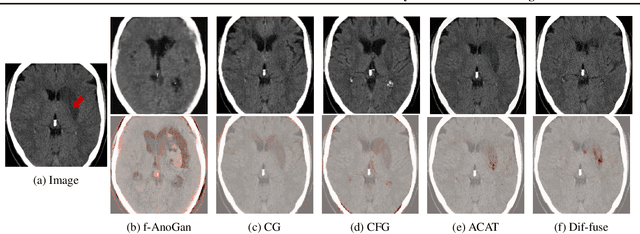

Abstract:Segmentation masks of pathological areas are useful in many medical applications, such as brain tumour and stroke management. Moreover, healthy counterfactuals of diseased images can be used to enhance radiologists' training files and to improve the interpretability of segmentation models. In this work, we present a weakly supervised method to generate a healthy version of a diseased image and then use it to obtain a pixel-wise anomaly map. To do so, we start by considering a saliency map that approximately covers the pathological areas, obtained with ACAT. Then, we propose a technique that allows to perform targeted modifications to these regions, while preserving the rest of the image. In particular, we employ a diffusion model trained on healthy samples and combine Denoising Diffusion Probabilistic Model (DDPM) and Denoising Diffusion Implicit Model (DDIM) at each step of the sampling process. DDPM is used to modify the areas affected by a lesion within the saliency map, while DDIM guarantees reconstruction of the normal anatomy outside of it. The two parts are also fused at each timestep, to guarantee the generation of a sample with a coherent appearance and a seamless transition between edited and unedited parts. We verify that when our method is applied to healthy samples, the input images are reconstructed without significant modifications. We compare our approach with alternative weakly supervised methods on IST-3 for stroke lesion segmentation and on BraTS2021 for brain tumour segmentation, where we improve the DICE score of the best competing method from $0.6534$ to $0.7056$.